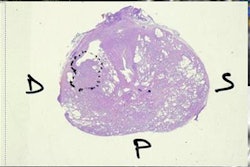

Investigators from Huazhong University of Science and Technology in Wuhan, China, and Yale University School of Medicine in the U.S. developed deep-learning software and compared its performance with a nondeep-learning method for differentiating prostate cancer from benign conditions such as benign prostatic hyperplasia (BPH) and prostatitis. In a study involving over 170 patients with over 2,600 prostate MR images, the group found the deep-learning software yielded significantly higher sensitivity and specificity.

To see if deep-learning technology might help, the researchers sought to compare the performance of deep convolutional neural networks with a nondeep-learning method called bag-of-words for fully automated classification of prostate cancer on MRI. The bag-of-word method represented the previous state-of-the-art for image recognition and analysis, and because the source code and implementation details were not available for prior commercial CAD algorithms, the team chose the bag-of-word method to provide a fair comparison with the deep-learning software.

Of the 172 patients included in the study, 79 had prostate cancer and 93 had benign conditions. The 93 benign cases included 75 with BPH and 18 with both BPH and prostatitis. The 172 patients had a total of 2,640 MR images.